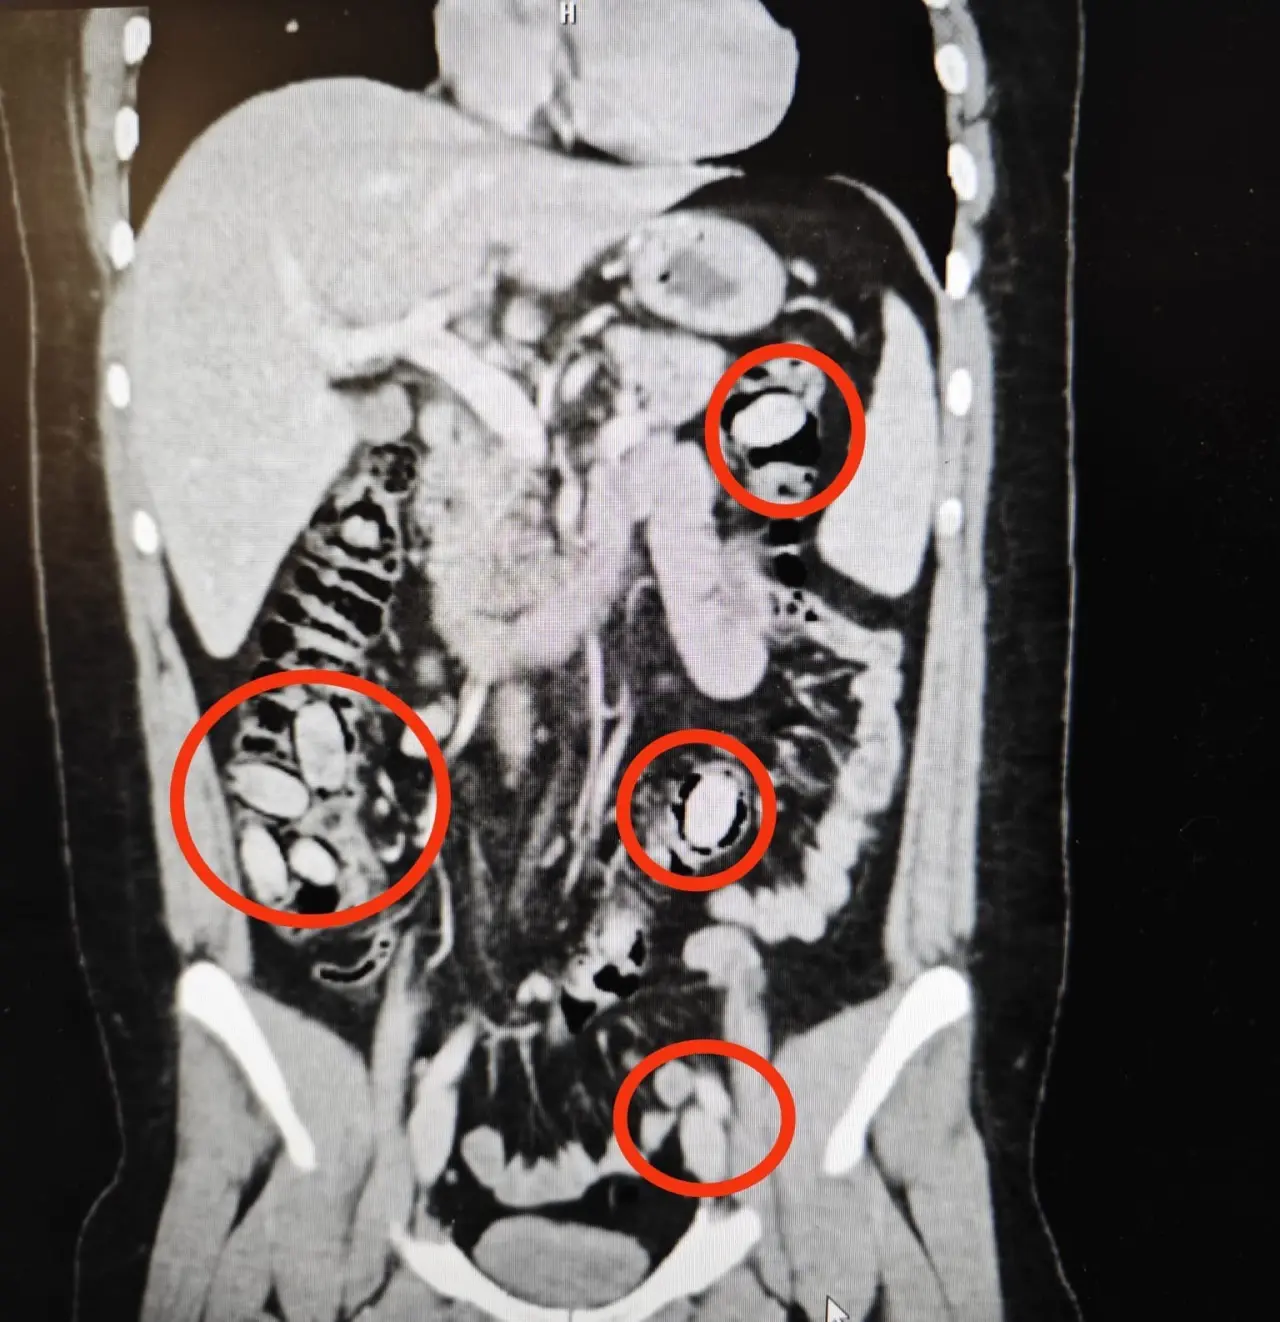

Polis ekipleri tarafından hastaneye sevk edilen şüpheliye yapılan detaylı tetkikler sonucunda, şahsın yutmak suretiyle midesinde 44 kapsül metamfetamin maddesi taşıdığı tespit edildi. Hayati risk taşıyan durum nedeniyle doktorlar tarafından acil cerrahi müdahale kararı alındı.

Gerçekleştirilen ameliyatla, söz konusu uyuşturucu kapsülleri şahsın midesinden çıkarıldı. Operasyonun başarılı geçtiği, kapsüllerin tamamının eksiksiz şekilde ele geçirildiği öğrenildi. Sağlık ekipleri, bu tür yöntemlerle uyuşturucu taşımanın ölümle sonuçlanabilecek ciddi riskler barındırdığına dikkat çekti.